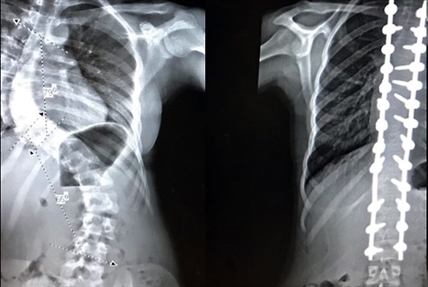

52 staples and 38 screws: Young Kelowna cheerleader recovering from emergency spine surgery

KELOWNA – A 13-year-old Kelowna cheerleader won’t have to give up her dream, thanks to…